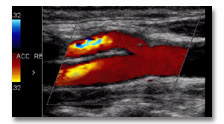

Duplex-Sonographie hirnversorgende Gefäße